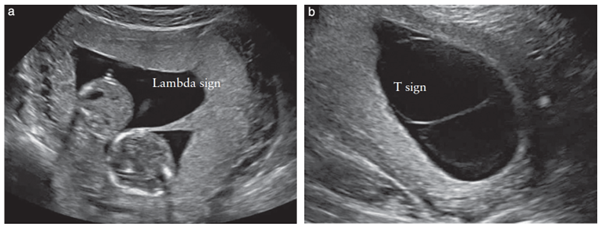

쌍태임신에서 단태임신과 구별되는 가장 중요한 것은 융모막과 양막의 개수를 확인하는 것이고 융모막성(chorionicity)는 임신 13주 6일 이전에 결정하도록 권고하고 있다(그림 1). 융모막성이 결정되는 시기에 양막성(amnionicity)도 결정하도록 하고 MCMA, 즉 단일융모막단일양막 쌍태임신의 경우 상급병원으로 전원하도록 한다.

그림 1. 임신 제1삼분기 초음파: (a) DCDA, dichorionic diamniotic twin pregnancy, in which the twins are separated by a thick layer of fused chorionic membranes; (b) MCDA, monochorionic diamniotic win pregnancy, in which the twins are separated by only two thin amniotic layers.